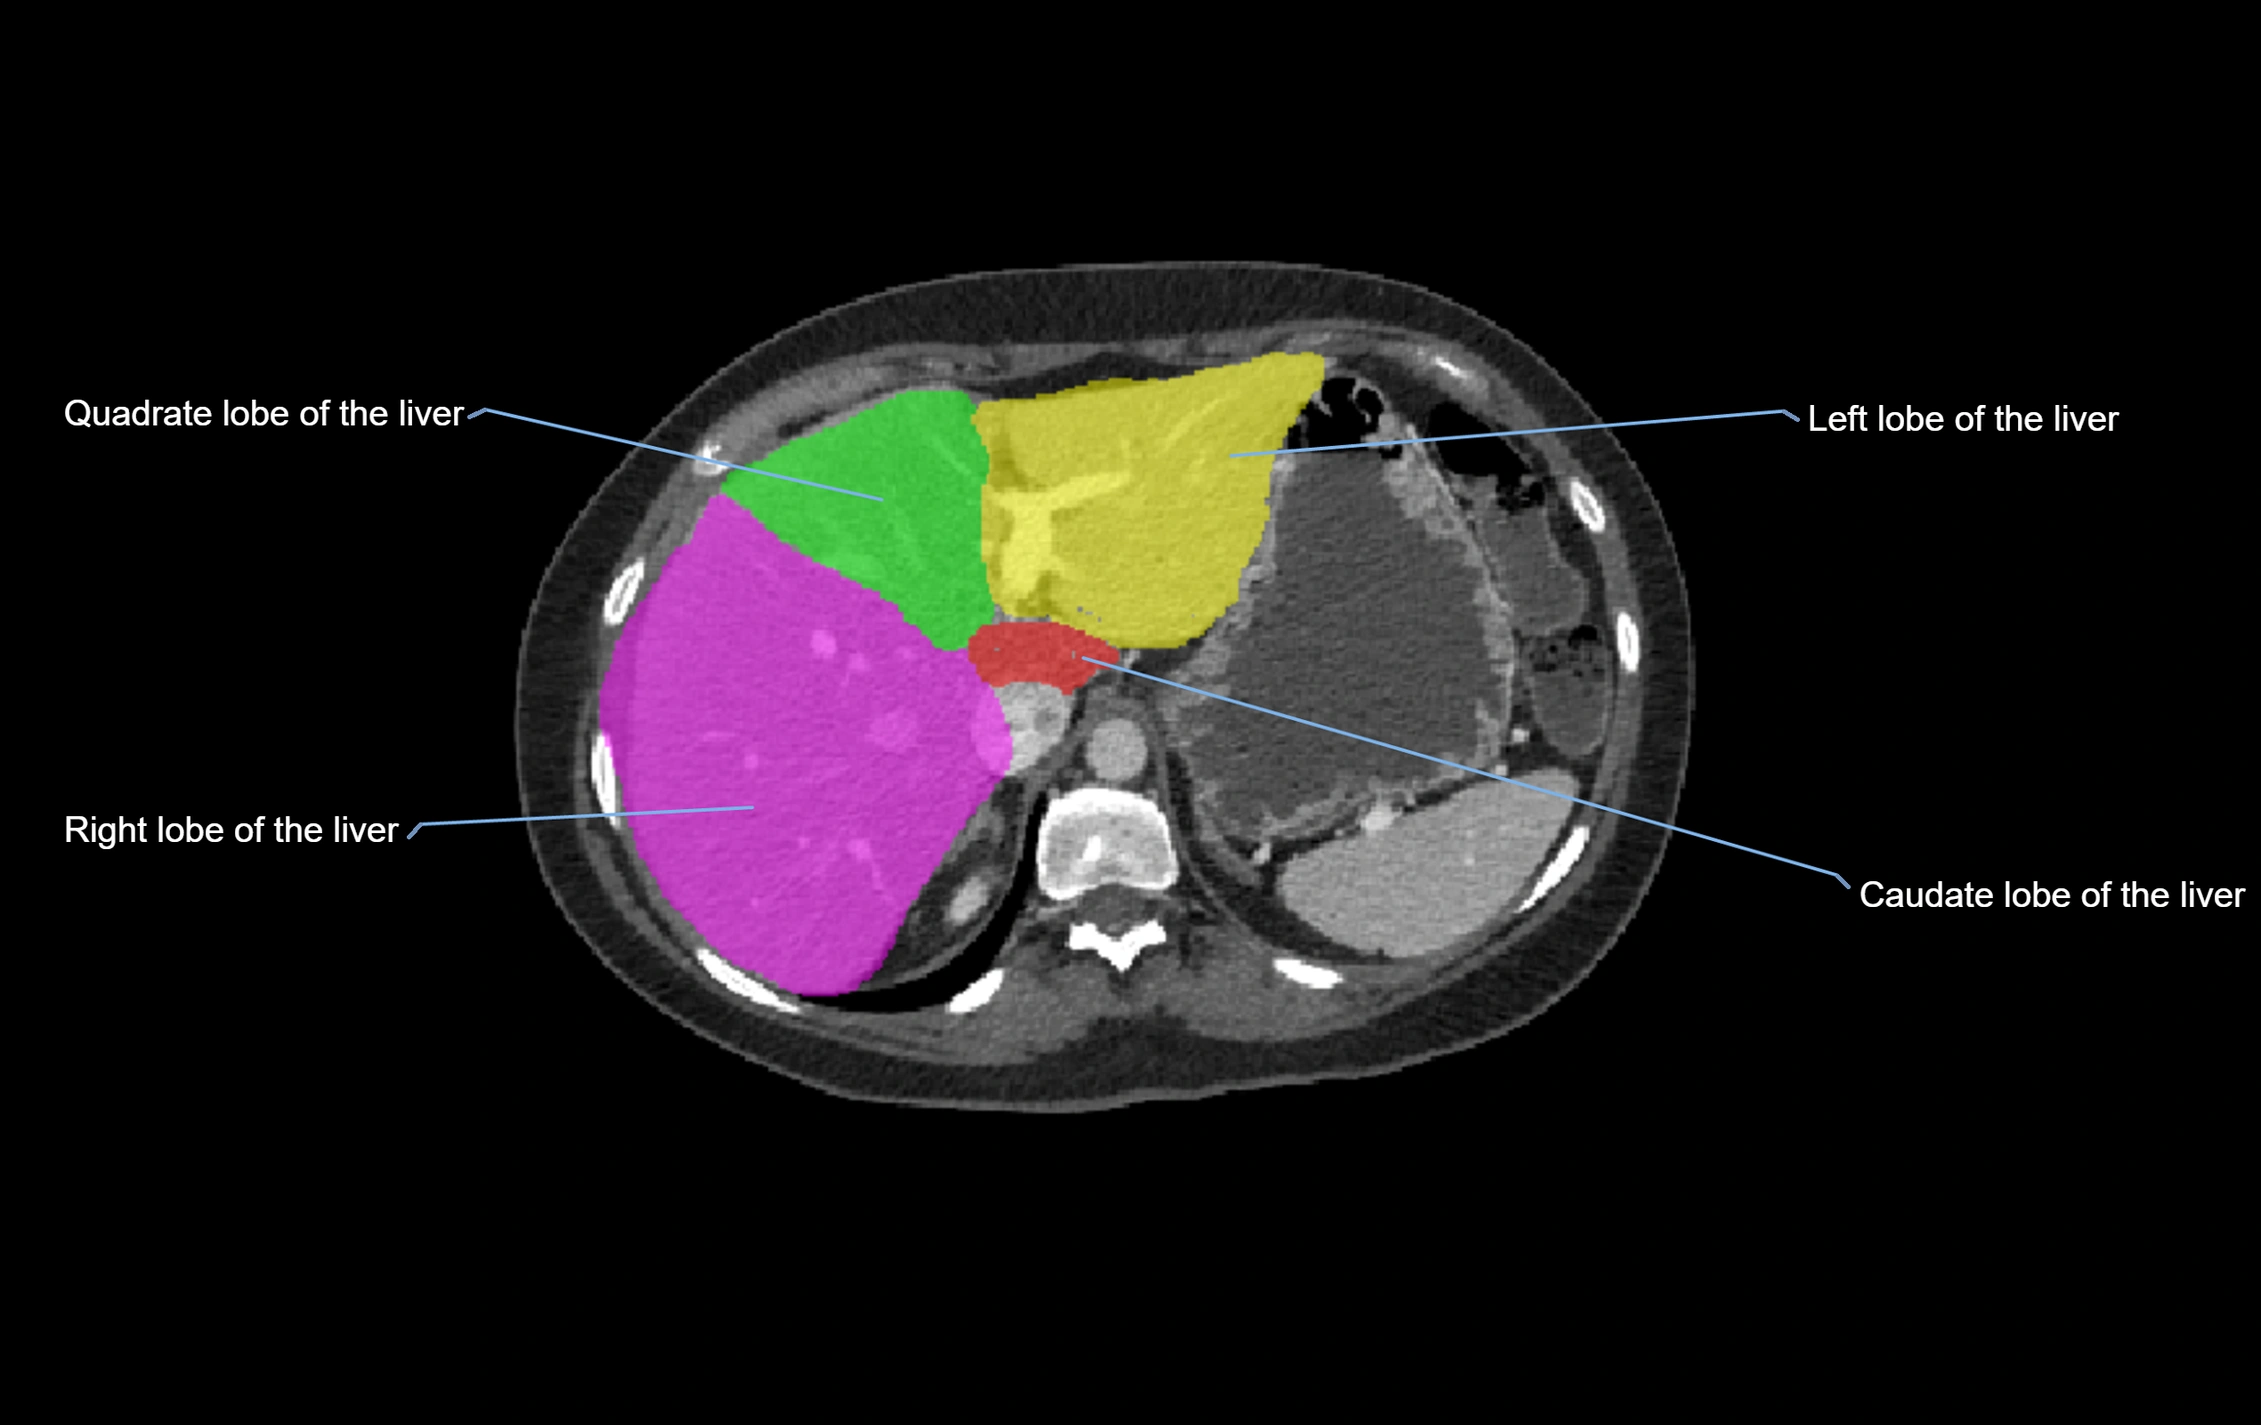

The caudate lobe of the liver is a distinct anatomical subdivision of the liver, designated as segment I in Couinaud’s classification. It lies on the posterior surface of the liver, between the fissure for the ligamentum venosum (left boundary) and the groove for the inferior vena cava (IVC) (right boundary). Superiorly, it is related to the posterior liver surface, and inferiorly it is separated from the left lobe by the porta hepatis.

The caudate lobe is unique because it receives dual portal venous and arterial inflow from both the right and left portal veins and hepatic arteries. It also has independent venous drainage directly into the IVC via multiple small hepatic veins, unlike other lobes that drain through the three main hepatic veins.

This anatomical autonomy makes the caudate lobe especially significant in liver surgery, transplantation, and hepatic venous outflow obstruction syndromes (e.g., Budd–Chiari syndrome). Enlargement of the caudate lobe is a characteristic imaging feature in chronic liver disease and cirrhosis.

CT Appearance

CT Pre-Contrast:

• Caudate lobe appears as a soft-tissue density, isodense to the rest of the liver

• Enlargement may be appreciated in cirrhosis or Budd–Chiari syndrome

CT Post-Contrast:

• Homogeneous enhancement in the portal venous phase, similar to rest of liver

• Independent venous drainage into the IVC may be visualized

• Lesions follow characteristic CT enhancement patterns (HCC: arterial hyperenhancement with washout; hemangiomas: peripheral nodular enhancement with centripetal fill-in)

CT Venous Phase (functional significance):

• Caudate lobe often enhances relatively more than other lobes in Budd–Chiari syndrome, due to preserved venous outflow

CT Image

image